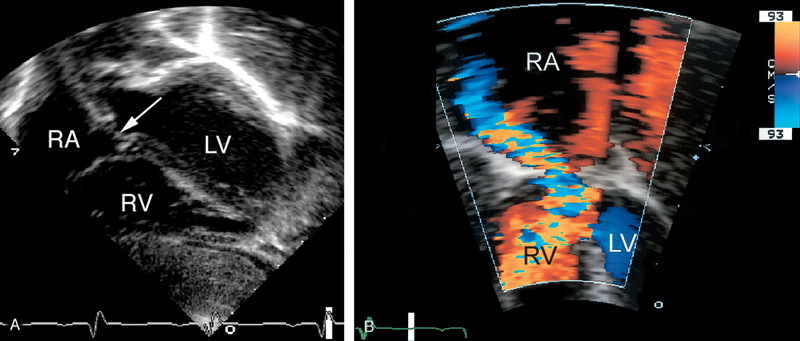

فحوصات تشخيصية لبعض امراض القلب والشرايين التاجية